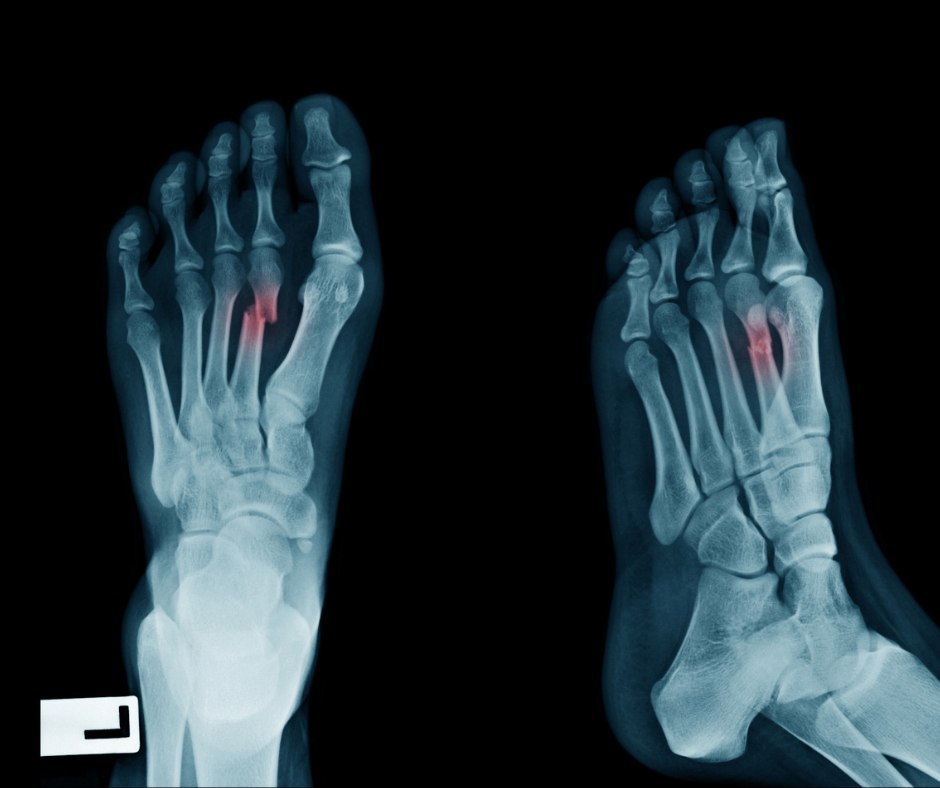

The first step is obtaining an accurate diagnosis. Keep in mind that stress fractures may not appear on an X-ray until weeks after they’ve formed, so relying solely on imaging may delay proper identification.